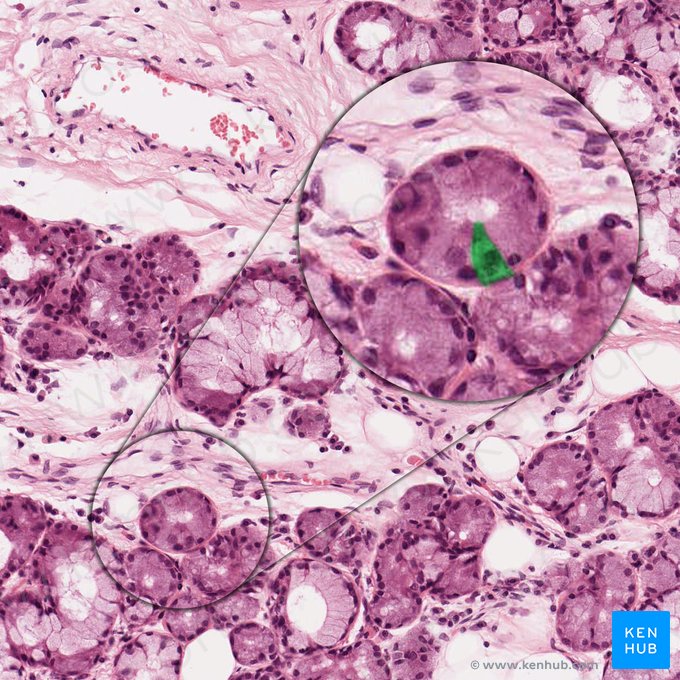

• Die Papillae fungiformes sind pilzförmig und beinhalten Geschmacksknospen auf ihrer Papillenkuppe.

• Die Papillae vallatae sind flach und von einem Wallgraben umgeben. In der seitlichen Papillenwand befinden sich eingelagerte Geschmacksknospen, während in den Wallgraben seröse von-Ebner-Spüldrüsen münden, die Nahrungsrückstände beseitigen.